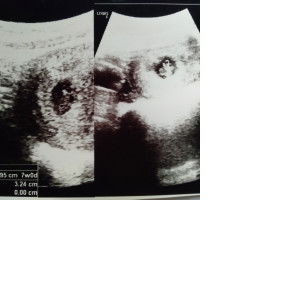

on the way ❤️